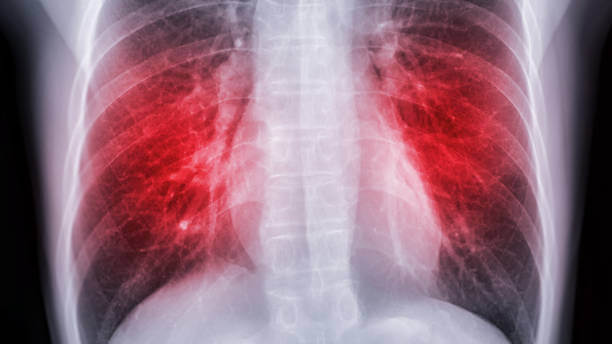

| 폐질환 | 폐색전증, 폐렴, 폐동맥고혈압, 기관지염, 폐암 |

폐색전증

객혈을 동반한 통증과 숨가쁨. 폐색전증으로 인한 통증은 가슴 옆으로 퍼질 수 있습니다. 혈전증은 혈전이 혈관에 생기는 질환이고, 색전증은 혈관을 막는 물질인 색전이 혈류를 타고 이동하다 혈관에 달라붙는 질환입니다.

폐색전증과 혈전증은 혈류를 방해하고 질병을 유발한다는 공통점이 있습니다. 혈관을 막는 이러한 것들은 막히는 위치에 따라 이름이 다릅니다. 뇌동맥이 막히면 뇌졸중, 심장동맥이 막히면 심근경색, 폐가 막히면 폐색전증이 됩니다.